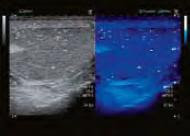

MicroPure is a unique technology that can assist you in confirming micro calcifications, a potential marker for malignancy in breast tumors.

“MicroPure is an adapted filter we put onto the image to burn out bright echoes so we can better visualize calcifications,” Erin Owen, Toshiba senior manager for clinical marketing in ultrasound, explains. “Ultrasound has never been really good at looking at microcalcifications. MicroPure puts a color on it to bring out the brighter echoes.”